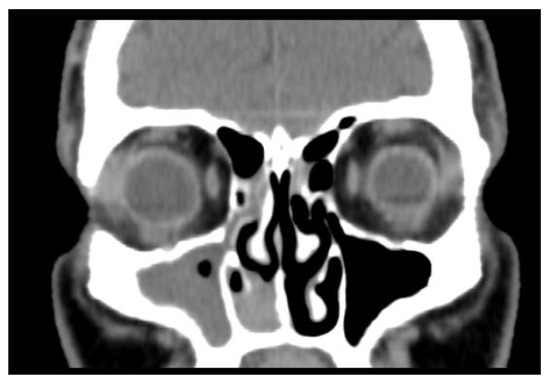

2. Case Report